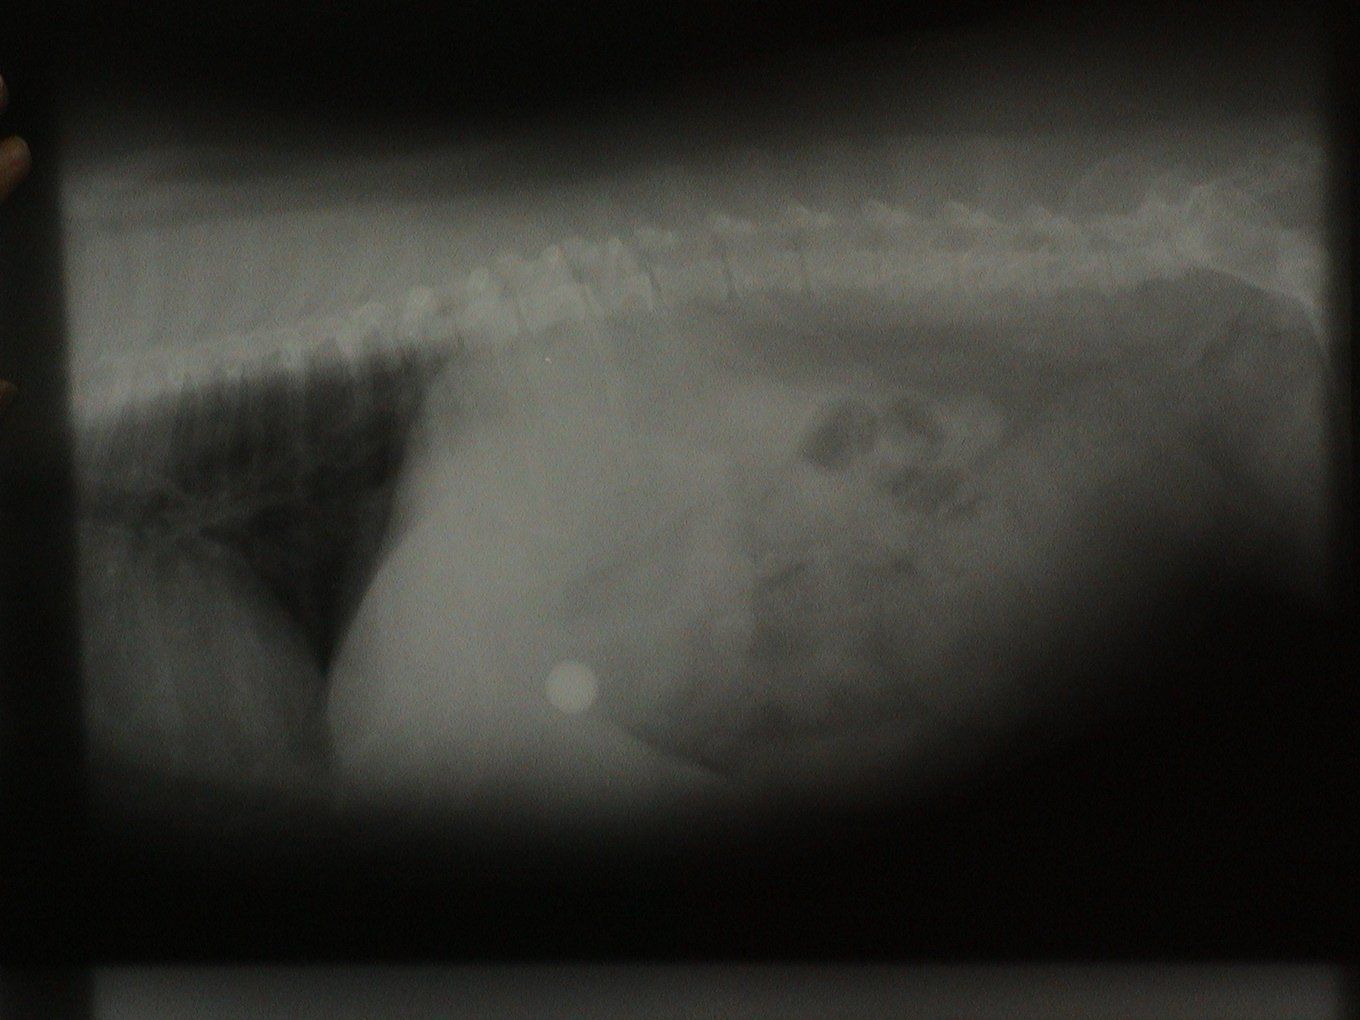

Let's identify the foreign bodies in each of these x-rays.